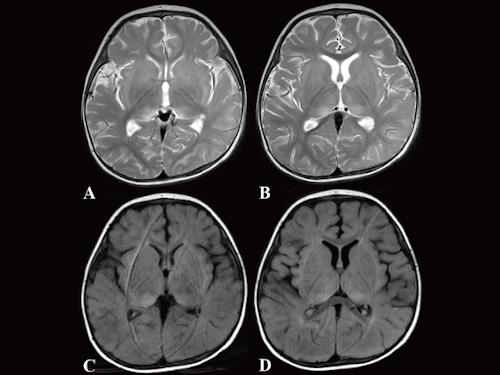

image: Brain MRI of the 10-month old boy with anti-NMDAR encephalitis obtained on day 4. The axial T2 weighted image (T2WI) in A and B and the axial fluid attenuation inversion recovery (FLAIR) image in C and D showed high intensity regions in the bilateral thalamus. New "immunity gene" mutations that researchers discovered to be deleterious were found in the infant.

A Hiroshima University-led research team detected two novel IRAK4 mutations, c.29_30delAT (p.Y10Cfs*9) and c.35G>C (p.R12P), in a 10-month-old boy with anti-N-methyl-d-aspartate receptor (anti-NMDAR) encephalitis and human herpesvirus 6 (HHV6) reactivation. The p.Y10Cfs*9 and p.R12P variations were inherited from his father and mother, respectively. The research team found the mutations by using whole exome sequencing (WES), a method used to exhaustively examine the DNA for genetic disorders.

Anti-NMDAR encephalitis, an inflammation of the brain, happens when the immune system attacks a vital brain receptor, causing psychiatric symptoms, involuntary movement, seizures, autonomic dysfunction, and central hypoventilation. It typically occurs in adult females suffering from ovarian tumor. Only a few cases of anti-NMDAR encephalitis have been so far reported in infants.